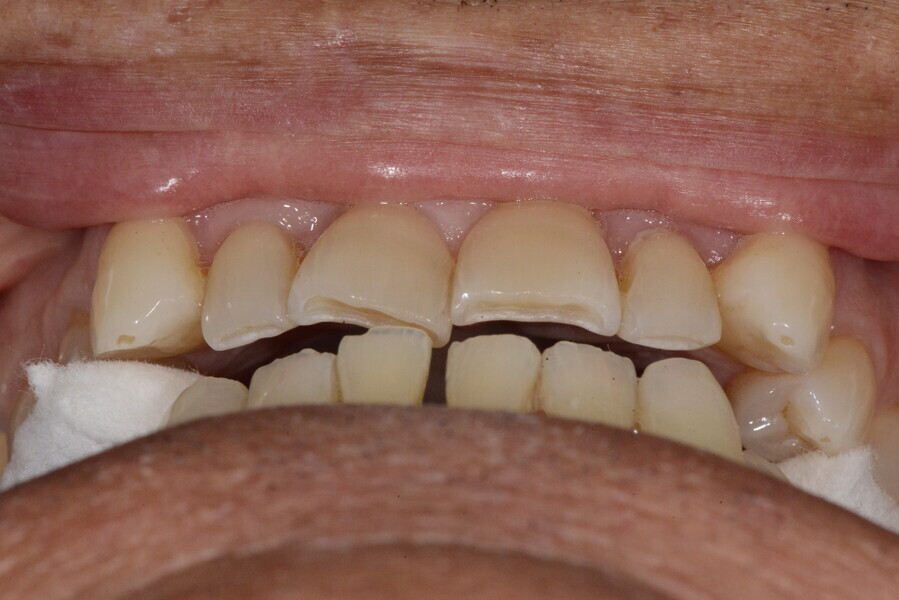

The 58-year-old patient wished to improve his oral aesthetics and function, complaining of mobility of the posterior teeth and wear of the anterior teeth. After data collection, a very complex situation was identified (Figs. 11–13):

1. severe periodontitis with poor prognosis of some teeth;

2. anterior crossbite;

3. severe wear mainly of the anterior teeth and compensatory eruption;38

4. atypical swallowing and lower posture of the tongue at rest;

5. masticatory dysfunction during the mastication test; and

6. no significant signs of temporomandibular disorder.

During the first visit, we checked the centric relation with cotton rolls, eliminating the posterior mesialising precontact and then performed a direct composite aesthetic and functional mock-up in this new position, not only to motivate the patient regarding the final result but also to help him understand better overall why tongue therapy, tooth alignment and dental resurfacing for augmentation of the vertical dimension of occlusion were required (Figs. 14 & 15).